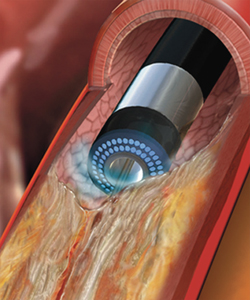

エキシマレーザー冠動脈形成術(ELCA)

冠動脈にレーザーカテーテルを挿入し、カテーテルの先端からエキシマレーザーを照射します。それにより、生体組織に損傷を起こすことなく病変組織を蒸散させることができ、狭窄・閉塞した血管を開通することができます。心筋梗塞など血栓が豊富な病変やステント再狭窄病変、完全閉塞病変、石灰化病変などに用いています。

画像提供:株式会社フィリップス・ジャパン